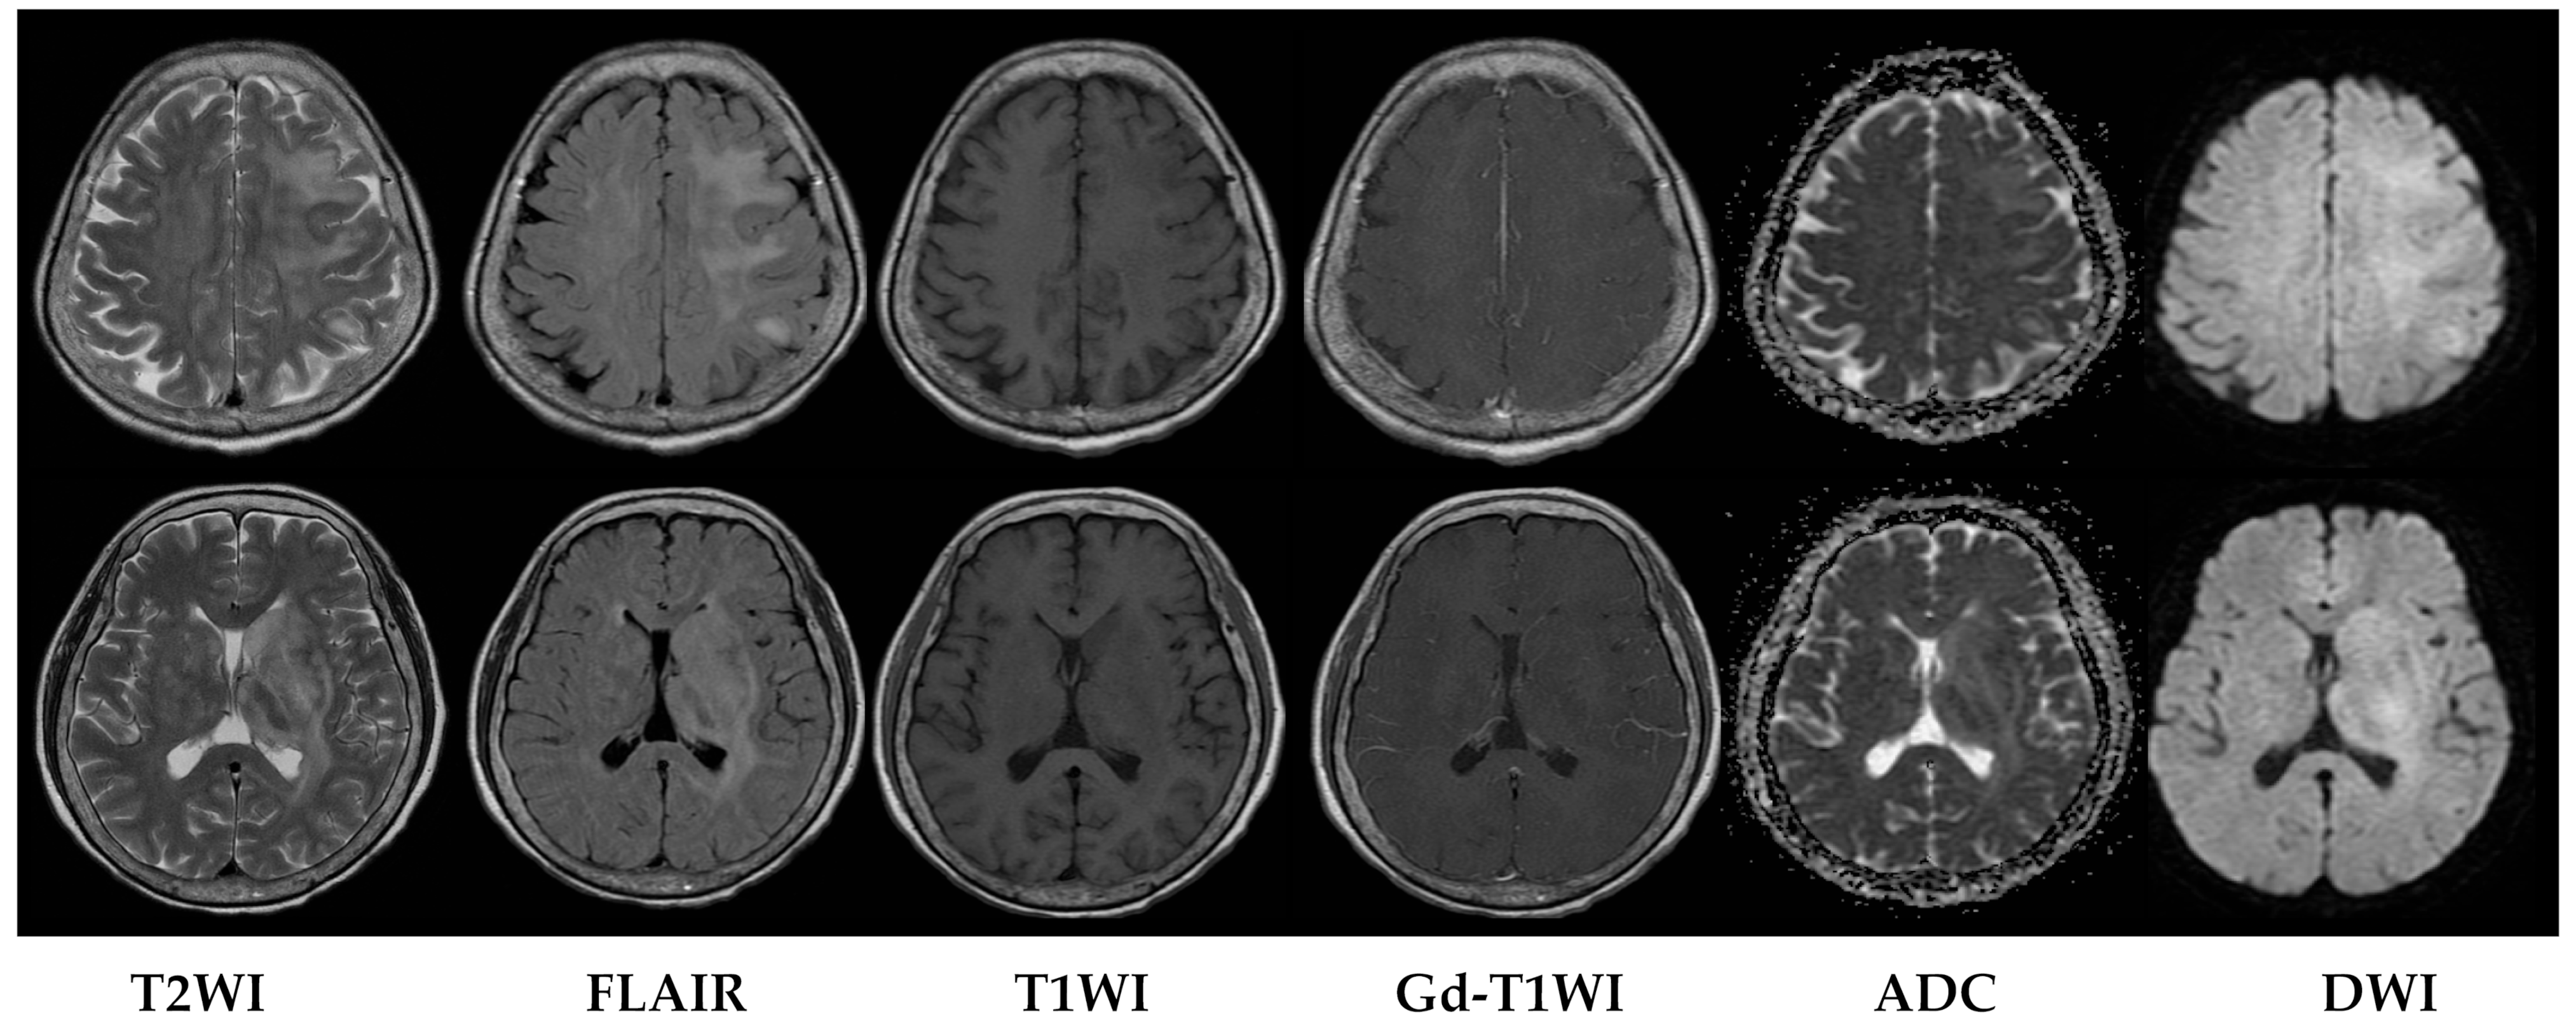

Upon evaluation, her fever persisted at 38.2 degrees Celsius, and laboratory investigations revealed leukopenia with a white blood cell count (WBC) of 610/μL. The urinalysis showed no evidence of pyuria, and the chest X-ray results were unremarkable. The treatment included the administration of Granulocyte Colony-Stimulating Factor (GCSF) for leukopenia and empirical antibiotics, specifically piperacillin/tazobactam, to address the neutropenic fever. An extensive infectious workup was conducted on admission, including a cerebrospinal fluid (CSF) analysis, which did not identify a clear infectious focus. The blood cultures yielded no bacterial growth. The patient’s WBC count elevated to 7430/μL after GCSF treatment. However, intermittent fever was still observed. Six days after admission, she exhibited a slow response and developed right-sided weakness. A relapse of CNS lymphoma or other CNS lesion was suspected. A brain computed tomography (CT) scan revealed abnormal hypointense changes in the left frontal lobe, left basal ganglion, left thalamus, and left cerebral peduncle with associated brain swelling (Figure 1). The subsequent magnetic resonance imaging (MRI), performed three days later, revealed hyperintensity in the left frontal and left parietal lobes, bilateral corona radiata, basal ganglia, and thalami, as well as the left temporal lobe and left-side brainstem on T2 weighted images (T2WIs), fluid attenuated inversion recovery (FLAIR), and diffusion weighted images (DWIs) without obvious restricted diffusion. No definite contrast enhancement was observed on the post-gadolinium T1 weighted images (Gd-T1WIs) (Figure 2). The presence of a mass effect from the infiltrative lesions, resulting in the compression of the left lateral ventricle and a midline shift to the right side, was observed. Notably, magnetic resonance spectroscopy (MRS) focused on the left basal ganglion lesion showed an elevated choline peak and decreased N-acetylaspartate (NAA) peak, with the presence of a lactate peak (Figure 3). A stereotactic brain biopsy for the left basal ganglion lesion and the left frontal lobe lesion confirmed the presence of diffuse large B-cell lymphoma, and the patient subsequently received whole-brain radiotherapy. Following treatment, the patient’s consciousness improved to an alert state (E4V5M6), and her right limb muscle strength showed improvement. Under stable conditions, she underwent another cycle of R-CHOP chemotherapy and completed whole-brain radiotherapy (WBRT). The patient was transferred to a nursing home under a stable clinical condition.

Figure 2. MRI performed three days after CT scan. MRI fused images of axial T2WI, FLAIR, T1WI, Gd-T1WI, ADC, and DWI images. Abnormal hyperintense lesions are seen at left frontal lobe, left parietal lobe, bilateral corona radiata, bilateral basal ganglia, bilateral thalami on FLAIR, DWI, and ADC images. No obvious contrast enhancement or restricted diffusion is seen.